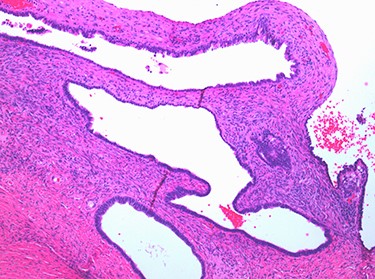

Multiple cysts of variable diameter lined by a single layer of epithelium, separated by ovarian stroma; haematoxylin and eosin stain, medium magnification, scale ×10.

The case emphasizes the diagnostic importance of histopathology, particularly in the setting of unanticipated and sinister macroscopic findings. The macroscopic appearances of the ovaries suggested malignancy diagnosis; however, the histopathology identified benign epithelial cysts [15]. The cyst lining was comprised of a single layer of epithelial cells amid normal ovarian stroma (Figs 6 and 7). The cysts contained normal serous epithelium with cilia lining the cyst lumen. These histological findings are consistent with the Müllerian phenotype and are therefore endosalpingiosis, ectopic tubal cell deposits on the surface of the ovaries, not that of hydrosalpinges or malignant ovarian cysts as the diagnostic rollercoaster suggested [15].